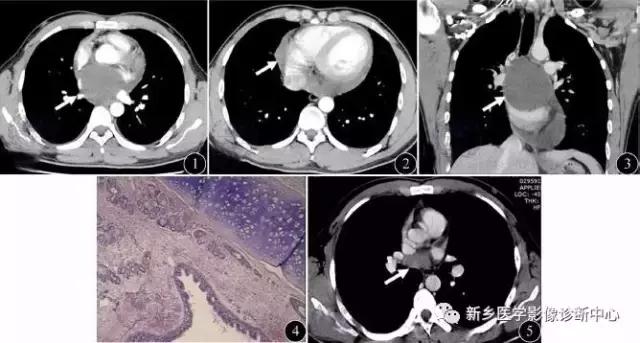

包虫囊肿

好发于肺中下野,继发感染时有发热,咳嗽胸痛,常见于牧区。圆形密度增高影,边缘清楚,内为水样密度,“水上浮莲征”为特征表现。

左图:右肺上叶小的破裂包虫囊肿,塌陷的棘球蚴包膜“水上浮莲征”

右图:充满整个右半胸腔巨大包虫囊肿。